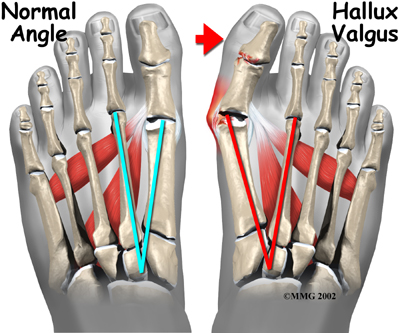

The term hallux valgus actually describes what happens to the big toe. Hallux is the medical term for big toe, and valgus is an anatomic term that means the deformity goes in a direction away from the midline of the body. So in hallux valgus the big toe begins to point towards the outside of the foot. As this condition worsens, other changes occur in the foot that increases the problem.

One of the other changes that occurs is that the bone just above the big toe, the first metatarsal, usually develops too much of an angle in the other direction. This condition is called metatarsus primus varus. Metatarsus primus means first metatarsal, and varus is the medical term that means the deformity goes in a direction towards the midline of the body. This creates a situation where the first metatarsal and the big toe now form an angle with the point sticking out at the inside edge of the ball of the foot. The bunion that develops is actually a response to the pressure from the shoe on the point of this angle. At first the bump is made up of irritated, swollen tissue that is constantly caught between the shoe and the bone beneath the skin. As time goes on, the constant pressure may cause the bone to thicken as well, creating an even larger lump to rub against the shoe.

One of the other changes that occurs is that the bone just above the big toe, the first metatarsal, usually develops too much of an angle in the other direction. This condition is called metatarsus primus varus. Metatarsus primus means first metatarsal, and varus is the medical term that means the deformity goes in a direction towards the midline of the body. This creates a situation where the first metatarsal and the big toe now form an angle with the point sticking out at the inside edge of the ball of the foot. The bunion that develops is actually a response to the pressure from the shoe on the point of this angle. At first the bump is made up of irritated, swollen tissue that is constantly caught between the shoe and the bone beneath the skin. As time goes on, the constant pressure may cause the bone to thicken as well, creating an even larger lump to rub against the shoe.